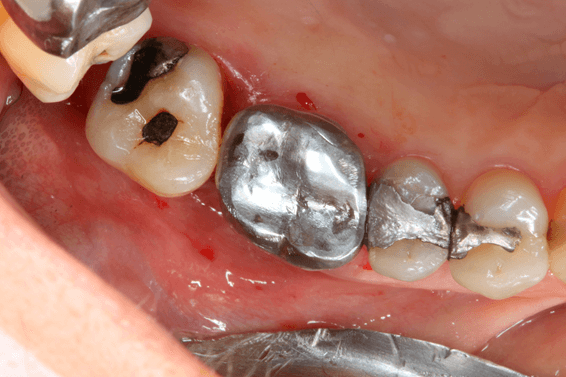

A preservação do alvéolo é uma opção de tratamento, evitando ou reduzindo a perda óssea. Alguns procedimentos são sugeridos com o objetivo de reduzir essa perda fisiológica, como a utilização de biomateriais preenchendo o alvéolo, barreiras, instalação de implante imediato entre outros. 4

Avaliamos o desempenho do biomaterial de hidroxiapatita com colágeno tipo I (Extra Graft XG-13®) na manutenção do volume alveolar.

A aplicação como o caso clínico abaixo se mostrou uma técnica acessível a todos cirurgiões dentistas, pois se trata de um procedimento de simples execução e acessível. Logo, deveria constar na clínica diária.